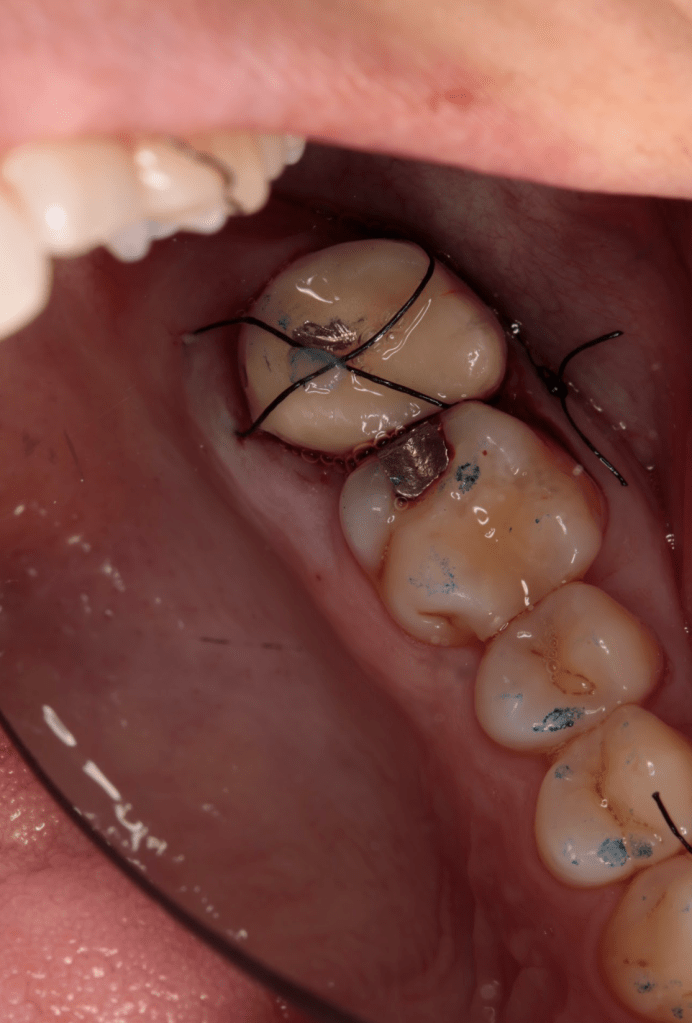

Fisura, remoción amalgama para explorar